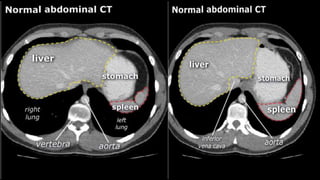

• A few characteristics of normal anatomy:

• Portal venous phase: the parenchyma of the

liver/spleen/pancreas is homogeneously enhanced.

• Intra-abdominal fat has the density of fat (HU -50 to -100;

see the X-ray/CT technique course for more information

about Hounsfield units); similar to normal subcutaneous fat.

If not, there may be ascites or fatty infiltration.

• A fewcharacteristics of normal anatomy: • Portal venous phase: the parenchyma of the liver/spleen/pancreas is homogeneously enhanced. • Intra-abdominal fat has the density of fat (HU -50 to -100; see the X-ray/CT technique course for more information about Hounsfield units); similar to normal subcutaneous fat. If not, there may be ascites or fatty infiltration.